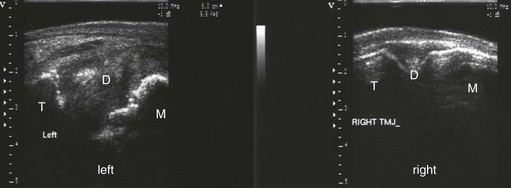

The equine TMJ is a synovial joint formed by the zygomatic process of the temporal bone and the condylar process, or condyle, of the mandible (Fig. 23.1).2,3 It is an incongruent joint and is divided completely into two separate compartments by an L-shaped, centrally concave, fibrocartilagenous disc (Fig. 23.1).2,47 The disc attaches circumferentially to the mandibular condyle, temporal bone, and joint capsule.5,6 The dorsal, discotemporal compartment is wider than the ventral, discomandibular compartment and apparently does not usually communicate with it,2,48 though in one study, communication between the compartments was demonstrated in three of seven cadaver heads injected with dye, indicating that in at least a small percentage of horses, they do communicate.9 Each compartment has a rostral and a caudal recess. The caudal recess of the discotemporal compartment is larger than the rostral recess, and the rostral recess of the discomandibular compartment is larger than the caudal recess.5,6,8 The joint capsule is reinforced by the lateral and caudal ligaments.5,6,8

Fig. 23.1 Anatomy of the temporomandibular joint (TMJ). The image on the left shows the skeletal components of the TMJ and a corrosion cast of the dorsal and ventral compartments with the fibrocartilagenous disk wedged between them. The right image shows a transverse section through the TMJ in a frozen cadaver specimen. T, temporal bone; M, mandibular bone; D, intra-articular disc.